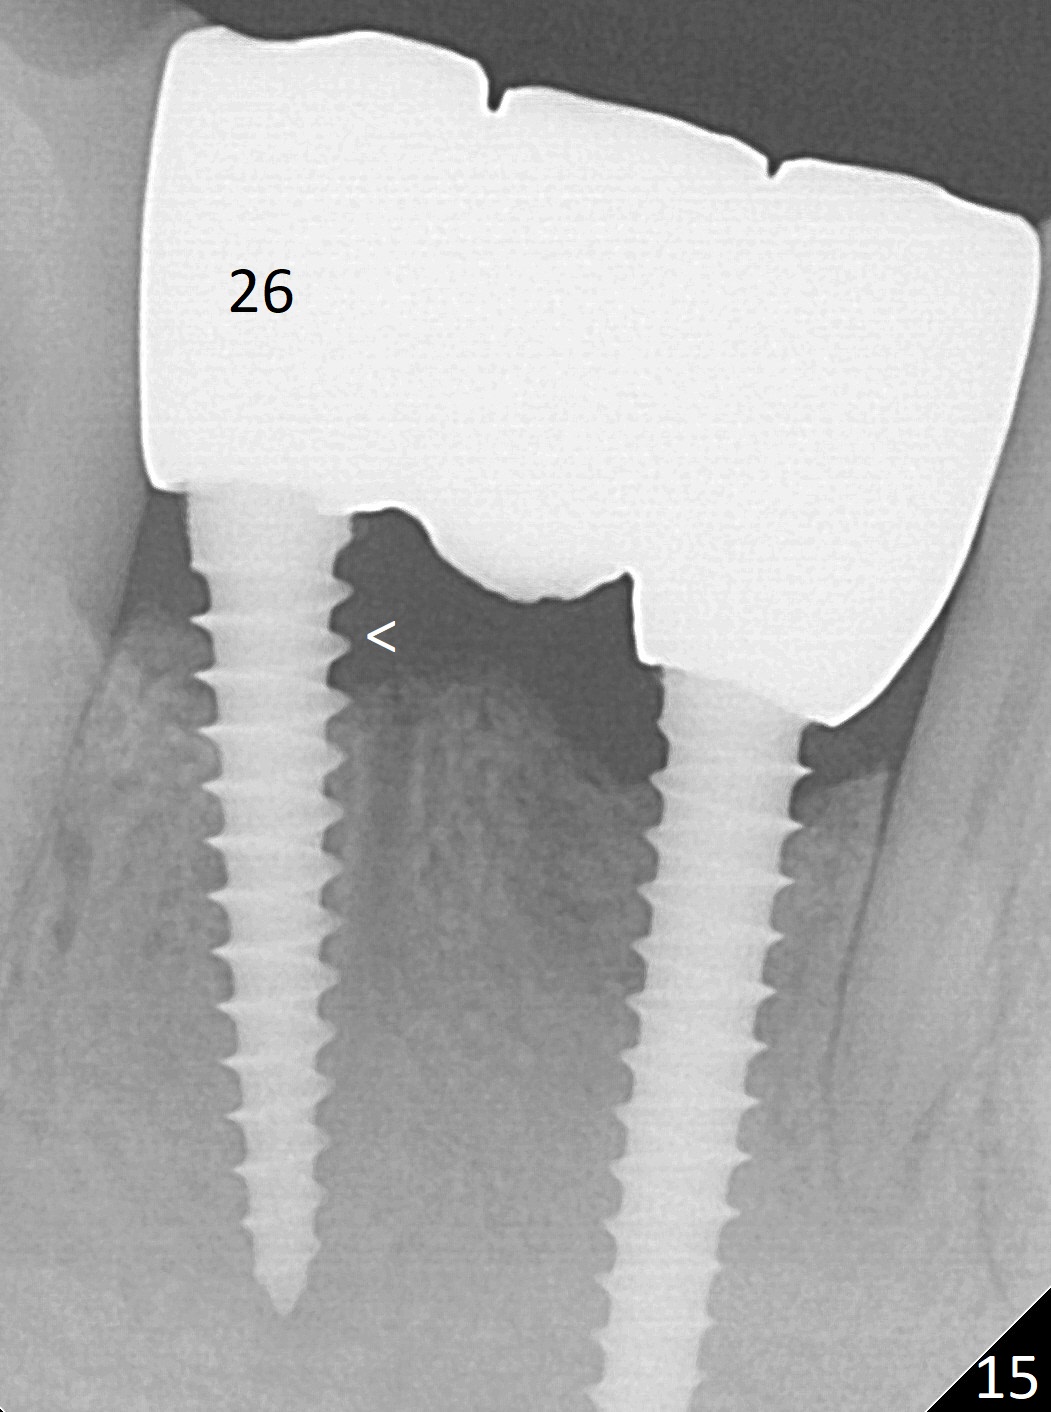

Fig.7 shows these two one piece implants immediately prior to cementation of the FPD (Fig.8). They are much more parallel to each other after prep, as compared to Fig.6. Fig.9 shows apparent bone growth around #24 implant (at the crest) 6,9 months post cementation and surgery, respectively. Orthodontic treatment will incorporate the fixed partial denture. Fig.10 shows that bone grows coronally (arrow) to cover 3 threads (from #6 thread to #3) at the site of #24 one year after functioning. There is mild buccal gingival infection involving #26 retainer. Preop CBCT is reviewed to determine whether it is related to potential thread exposure. It appears that at the sites of #24 (Fig.13,14) and 26 (Fig.11,12), 2.5 mm implant is more appropriate for the narrow ridge than 3.0 mm one. In fact, periimplantitis develops at #26 two years of absence of perio maintenance (because of atrial fibrillation with blood thinner; Fig.15, 3 years 7 months post cementation). Periimplantitis persists 4.5 months later. Although water pik is purchased, it is not used often because of low blowing force. If needed, remove the FPD atraumatically. Unwind the implant, clean the coronal threads with Titanium brush or remove the exposed threads and replant the implant with bone graft.